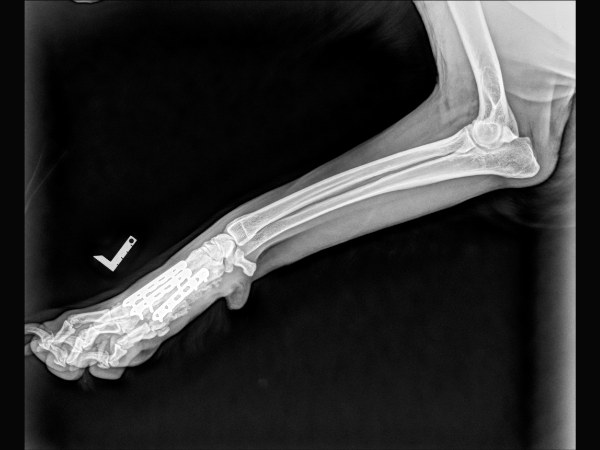

<術後のレントゲン>

インプラントによる内固定を行いました。

▼術後